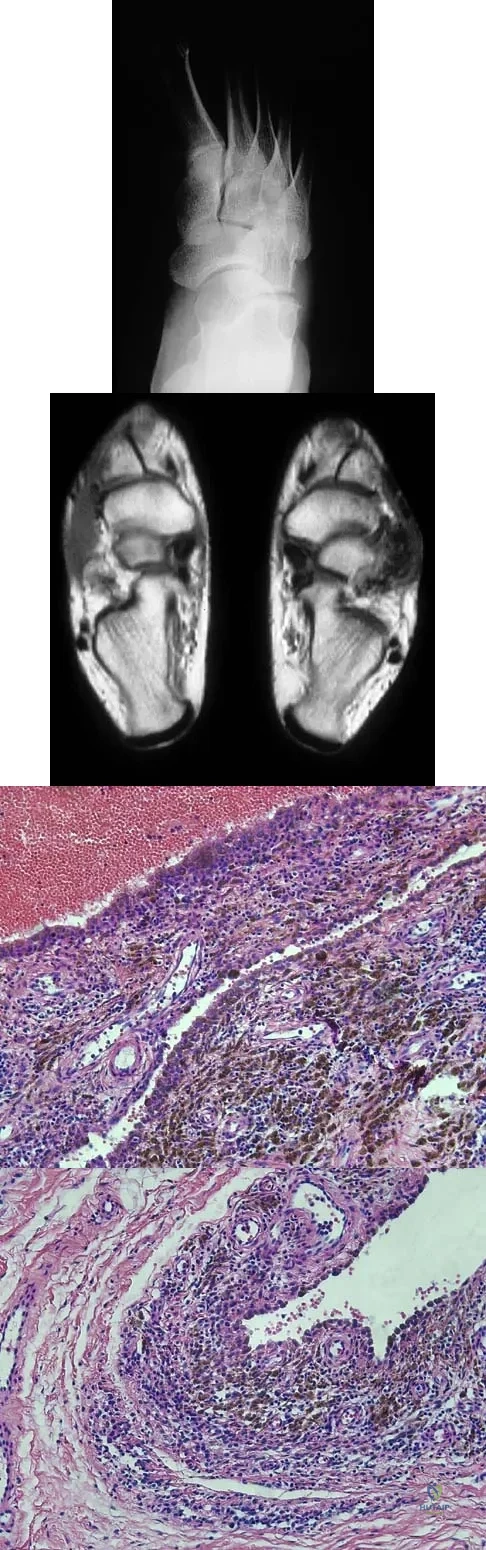

A 16-year-old girl has a painful foot mass. A radiograph, MRI scan, and biopsy specimens are shown in Figures 35a through 35d. What is the most likely diagnosis?

Explanation